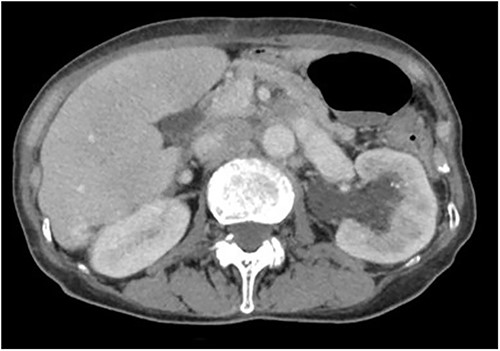

A 78-year-old woman (height, 161 cm; weight, 35 kg) had undergone total gastrectomy for gastric cancer; pathological examinations had revealed signet ring cell carcinoma with invasion into the serosa. One year and 4 months after the surgery, she presented to our hospital with fever, anorexia and weight gain. Computed tomography (CT) revealed left ureteral stricture and hydronephrosis caused by recurrent peritoneal dissemination (Fig. 1). Blood tests revealed decreased renal function and an increase in the inflammatory response. Based on these findings, a diagnosis of left obstructive acute pyelonephritis was made, prompting a decision to place a ureteral stent to relieve the obstruction. Using a flexible cystoscope fluoroscopically, a 6 Fr, 24 cm double-J ureteral stent was inserted into the left ureter. The guidewire passed smoothly, and good coiling was achieved both proximally and distally with no apparent complications (Fig. 2). Two weeks after stent placement, the patient recovered with improvements in left hydronephrosis and renal function.

Abdominal CT scan; (a) CT demonstrates the position of proximal coil formation in the left renal pelvis; (b) CT demonstrates proximal stent migration into the ureter.